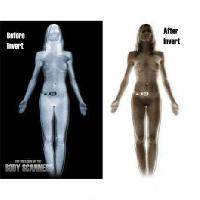

Изучение проблемы низкого качества рентгенограмм на Вашем оборудовании.

Мобильный рентгенаппарат + оцифровщик. Получение рентгеновского изображения на экране ноутбука. Вариант за 1,4 миллиона рублей под ключ.